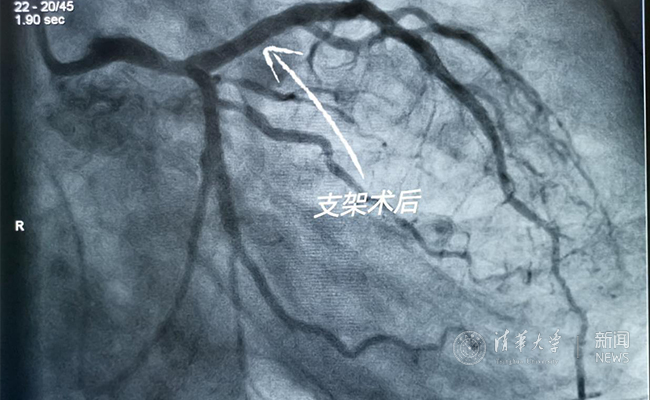

患者术后造影

此次手术过程历时仅30分钟即完成支架植入。患者是一位58岁中年男性,前降支金属支架2次再狭窄,术中在前降支充分预扩张后顺利植入3.5×21mm生物可吸收支架1枚,术后即刻造影显示扩张良好。